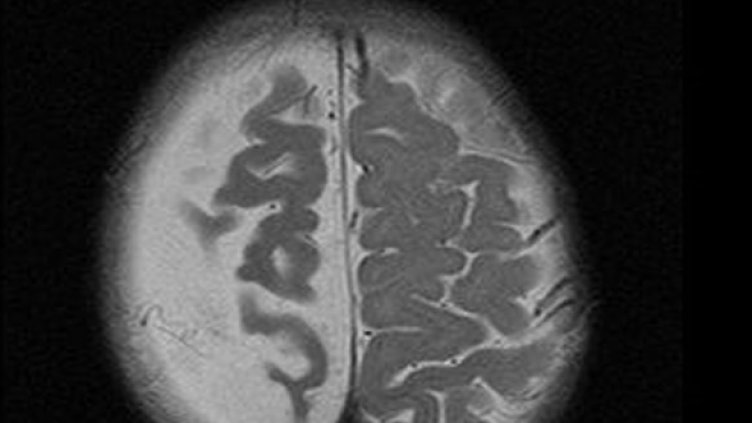

Специалистите сравнили резултати от сканиране на мозъка на педофили, излежаващи присъди за престъпленията си, и престъпници, извършили други дейния извън закона.

В мозъка на педофилите имало много по-малко от т.нар. бяло вещество, което представлява нервни влакна, свързващи различните сфери на главния мозък. Намира се по повърхността на продълговатия мозък, моста, средния и междинния мозък. Бялото вещество образува центровете на някои важни дейности на организма.

Според резултатите от изследването най-съществени били отклоненията в броя нервни влакна, които осигуряват връзката между шестте зони на главния мозък, отговарящи за половата възбуда и регулирането на сексуалните импулси.

Тази особеност в строежа на мозъка води до това, че педофилът не може да направи разлика между приемливите и неприемливите обекти на сексуалното си влечение.